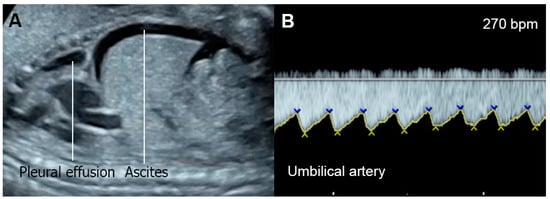

| Normal | −1 Point | −2 Points | |

|---|---|---|---|

| Hydropic signs | Absence of effusion | Abdominal or pleural, or pericardial effusion | Skin edema |

| Venous Doppler (umbilical vein: UV & ductus venosus: DV | Normal Doppler UV ![]() DV ![]() | Reversed ductus venosus flow UV ![]() DV ![]() | Pulsatile flow in the umbilical vein UV ![]() |

| Heart size (Cardio-thoracic ratio) | ≤35% | 35–50% | >50% or <20% |

| Cardiac function | Normal function | Holosystolic TR, or ventricular shortening fraction < 28% | Holosystolic MR or TR dP/dt < 400, or monophasic inflow |

| Arterial Doppler (umbilical artery) | Normal Doppler![]() | Absent end-diastolic flow![]() | Reversed end-diastolic flow![]() |